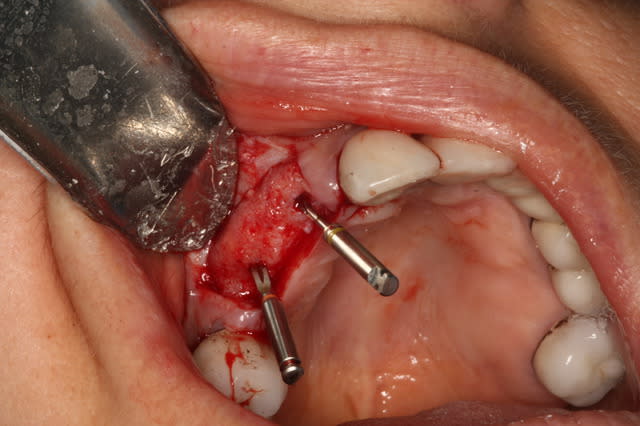

Ce sera un bridge sur 2 implants

Il y avait pas de gencive attachée au buccal de la zone.

Greffon AlloDerm, 2 pins au centre (car je ne voulait pas taper dans les implants, extension-tunnel en mésial et distal, sutures.